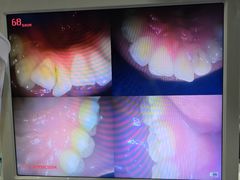

• 土豆口腔(凤凰北总店)

Tiff08050715 | 24-02-08